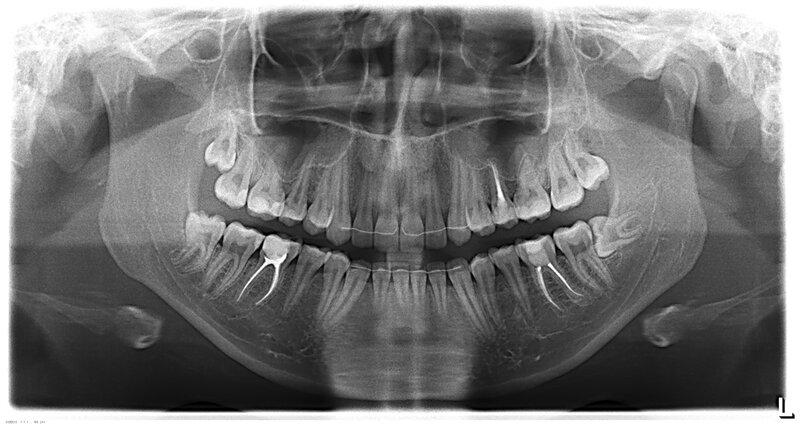

Рисунок 3 - Рентгенография зубо-челюстной системы пациента без отклонений от нормы